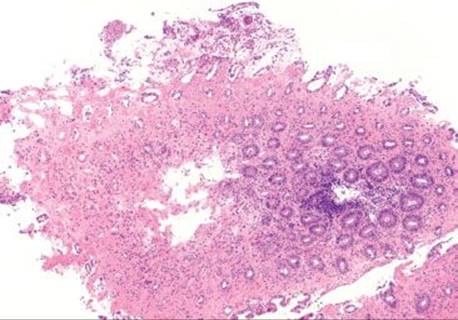

Figure 4.56 Ischemic colitis pattern. Note the microcrypt pattern of injury at scanning magnification. There is a gradient of crypt withering and dissolution that worsens as the surface epithelium is approached. Also, note the relatively homogeneous pink appearance of the hyalinized lamina propria.

Decreased blood flow and lack of oxygen to the GI tract result in necrosis or tissue damage, causing ischemia. There are several weak points in the colonic blood supply, known as watershed areas, which result from incomplete anastomosis of the marginal arteries and lack of sufficient collateral circulation. These watershed areas are more vulnerable to ischemic injury than other parts of the colon and include the splenic flexure (or Griffith’s point), the rectosigmoid region at Sudeck’s point, and the ileocecal region. Among the older population, ischemic disease is typically attributable to atherosclerotic mesenteric vascular disease, but the causes of colonic ischemia are many (Table 4.2). The histologic findings are dependent on the timing of the ischemic event (Figs. 4.52–4.63). Early and minimal injury, for example, occurs first as degeneration and sloughing of superficial epithelial cells, edema, and vascular congestion. Later, the epithelial cells become markedly attenuated and the crypts appear compressed and atrophic (“microcrypts”) as the lamina propria swells and hemorrhages. Within 5 hours of total acute vascular occlusion, almost the entire intestinal wall appears necrotic. These changes are devoid of acute inflammation until reperfusion occurs. Paradoxically, reperfusion further injures the tissues by introducing oxygen free radical formation,16 the severity of which is dependent on the duration of the preceding hypoxia.

Mucosal ischemia causes a highly characteristic pattern of injury, including features of surface injury, loss of mucin, lamina propria hemorrhage and hyalinization, withered crypts, atrophic microcrypts, and lamina propria collapse (Fig. 4.50). The architectural pattern of withered crypts and microcrypts is distinctive at low magnification, and one might even refer to this pattern of injury as the “microcrypt pattern” (Fig. 4.51). Although ischemic injury is top among the differential diagnoses, other considerations include vascular injury (such as that seen in radiation colitis, amyloidosis, or vasculitis), infection (particularly Escherichia coli 0157:H7 and Clostridium difficile), and medications (NSAIDs, Kayexalate, and sevelamer).